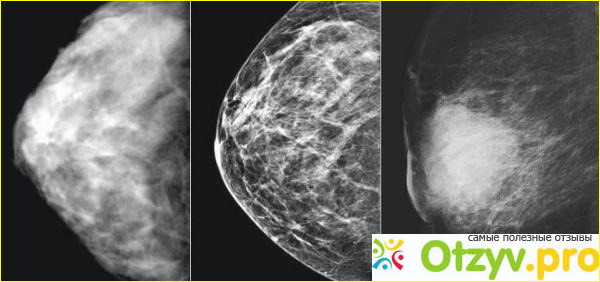

Конечно, обслуживание, диагностика там на высшем уровне, не то что у нас было — беготня по кабинетам, масса

непонятно каких анализов, месяц только определяли какой у неё диагноз и кто и где должен ею заниматься. В

Берлине ей всего за неделю всё точно смогли сказать, провели диагностику и установили, что у неё,

действительно, рак молочной железы только 3 ст. с метастазами в подмышку, но заверили в благополучном

исходе, так как не в первой они занимаются подобными видами лечения.